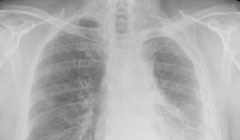

Inhaling or ingesting asbestos can lead to serious health issues such as mesothelioma cancer, asbestosis, pleural plaques and asbestos lung cancer.